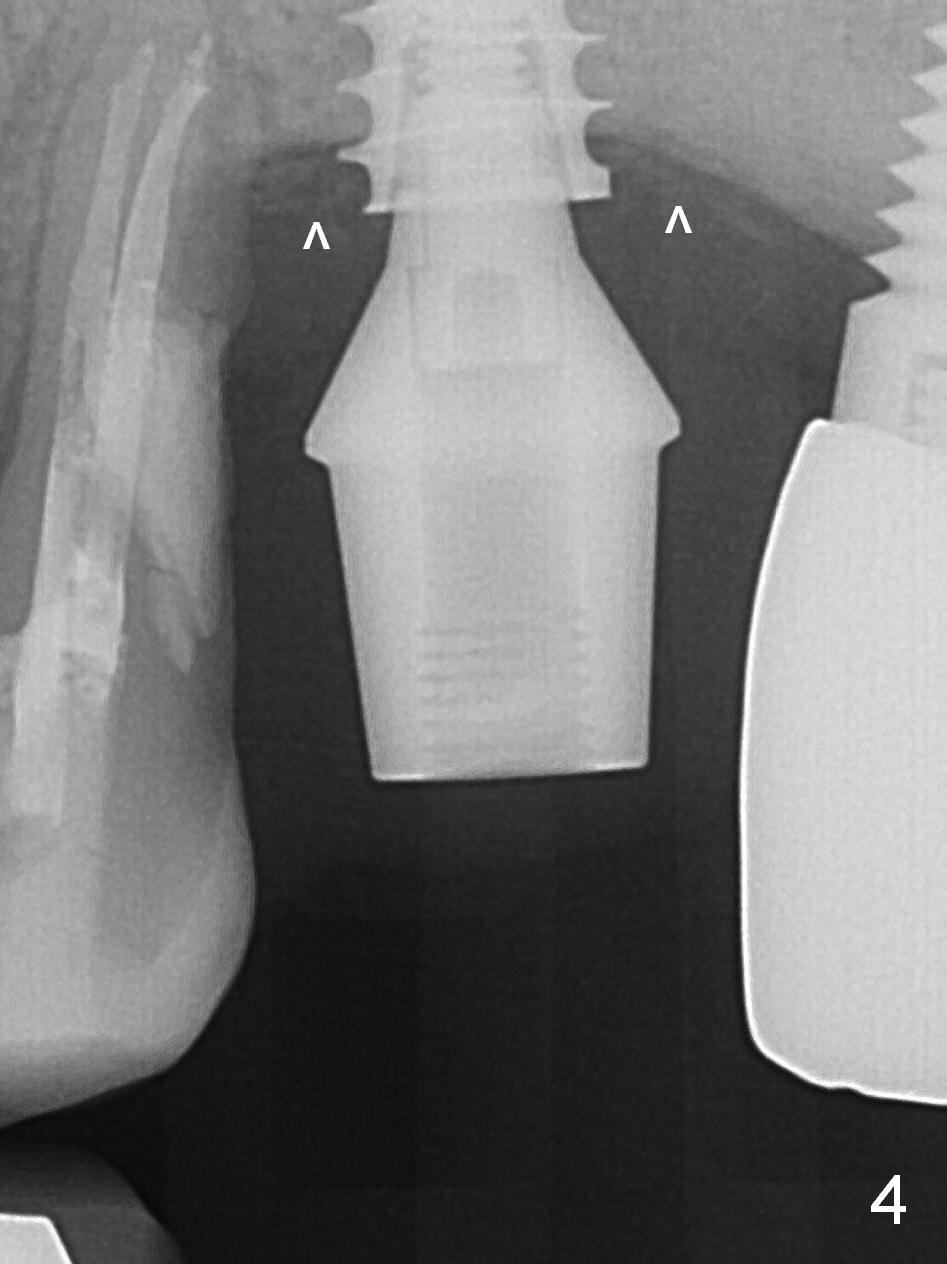

Four months post bone graft, the bone height at #14 is ~ 5 mm (Fig.1). After osteotomy for 4 mm with 4.3 mm Magic Drill (hard bone), Magic Sinus Lifter is used for sinus lift for ~ 8 mm without sinus membrane perforation. Perforation occurs with pulsating hemorrhage after sinus lift with allograft (.5-1 mm, mixed with Metronidazole). Collagen plug is used to repair the perforation before placing a short (5x7 mm) IBS implant with ~ 25 Ncm (Fig.2). After placing a 6.5x5.7(3) mm abutment, allograft is placed around the most coronal exposed implant thread (^). Acrylic is applied over the abutment for wound protection. There is mild nasal hemorrhage for 2 days postop. To prevent and treat sinus membrane perforation, PRF will be routine prepared preop for future cases. New bone forms apically and coronally 4.5 months postop (Fig.3,4 ^). A new temporary crown is fabricated so that it can undergo progressive loading for a few months before final impression. The definitive restoration is delivered 7.5 months postop (Fig.5). The bone density apical to the implant becomes apparently denser nearly 5 months post cementation (Fig.6). The bone density in the crest increases 2 years post cementation (Fig.7 *).